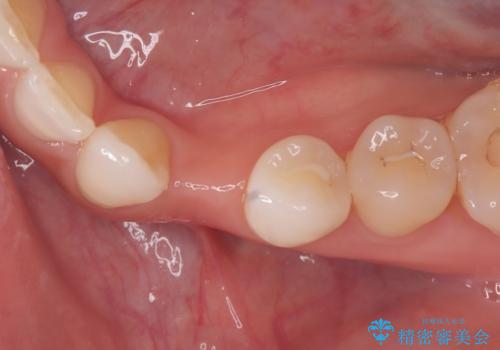

- 左下の歯が生まれつき無かった患者様です。

矯正治療にてスペースを一箇所に集めてからオールセラミックブリッジにて補綴治療を行いました。

今回は、患者様の希望もありインプラントではなくブリッジにて修復しています。